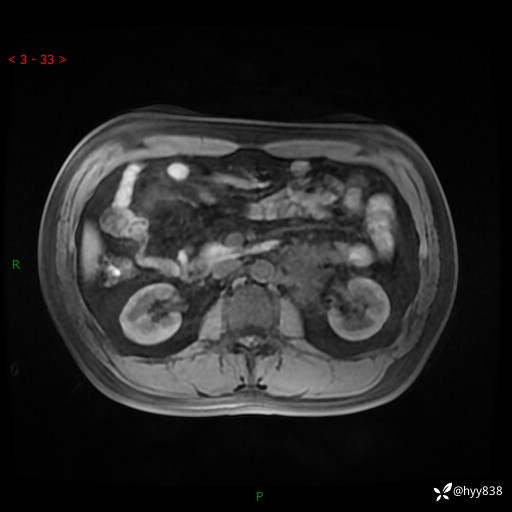

现病史:患者3月余前检查发现左侧腹膜后占位,大小约3.7*4.9cm,平素无腰疼,无肉眼血尿,无尿频尿急等不适,当时未特殊处理,在门诊复查CT提示左侧腹膜后占位,门诊拟“左侧腹膜后占位”收入院。 起病以来,患者精神佳,饮食、睡眠良好,大小便正常,体力体重无明显变化。

MRI增强